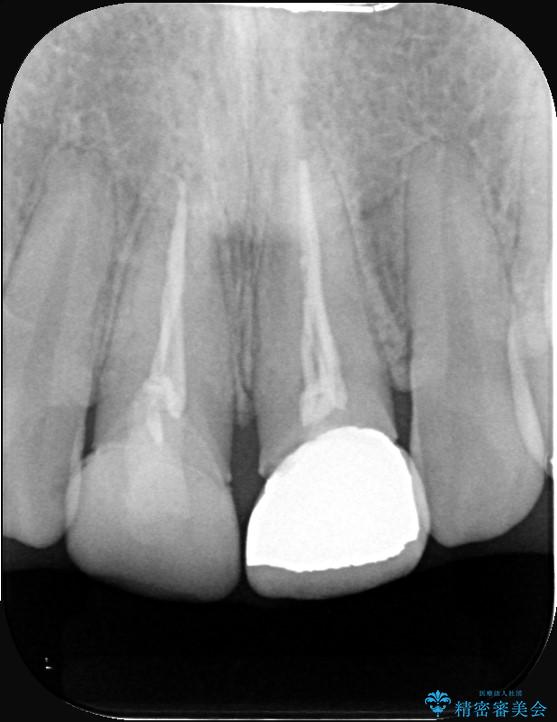

精密検査の結果、単に被せ物が合っていないだけでなく、その下の歯の根の治療(根管充填)が不十分で、再感染のリスクが高いことが分かりました。そのため、被せ物を新しくする前に、まず顕微鏡などを用いた精密根管治療を行いました。その上で、最も見た目が自然なオールセラミッククラウンで修復する計画です。これにより見た目の改善と歯の寿命の長期化を目指しました。

治療は、再感染の原因となっていた粗な根管充填材を丁寧に取り除く精密根管治療から開始しました。治療中はラバーダムと歯科用顕微鏡を使用し、根管内を徹底的に清掃・消毒。根の先まで緊密に薬を詰めることで、再発リスクを最小限に抑えました。根管治療の完了後、歯ぐきの状態を整え、周囲の歯と調和するオールセラミッククラウンを作製。金属を一切使わないため、透明感のある自然な仕上がりとなり、長年の見た目のコンプレックスも解消。歯の内部から表面までを根本的に改善することができました。